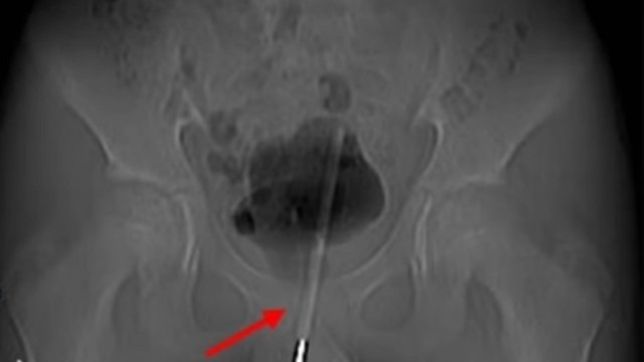

A criança não identificada foi levada às pressas para o hospital depois de inserir o dispositivo médico em seu pênis enquanto se masturbava e sofreu fortes dores por cerca de nove horas. Raios-X revelaram que o termômetro havia sido inserido tão profundamente no trato urinário que na verdade havia entrado na bexiga do menino. O caso foi detalhado no Asian Journal of Surgery.

Preocupados com os danos que o termômetro poderia gerar nos órgãos do menino caso fosse tirado da forma como entrou, os médicos decidiram fazer a extração pela bexiga da criança por meio de uma cirurgia. O menino, da cidade de Chengdu, no centro da China, admitiu aos médicos do Primeiro Hospital Popular do distrito de Longquanyi que havia inserido o termômetro para obter prazer sexual, uma prática arriscada conhecida como sondagem.

A sondagem acarreta múltiplos riscos, como o objeto ficar preso ou perdido, como no caso do menino, danificar ou cicatrizar os tecidos internos e perfurar a bexiga. Algumas dessas lesões podem ocorrer quando os médicos removem o item ou fazem a cirurgia na própria bexiga, daí a cautela dos cirurgiões neste caso. Eles fizeram um pequeno orifício cirúrgico no tecido até a bexiga, que armazena a urina, e inseriram pequenas ferramentas para manipular o termômetro no ângulo e na posição corretos para retirá-lo pelo buraco criado.